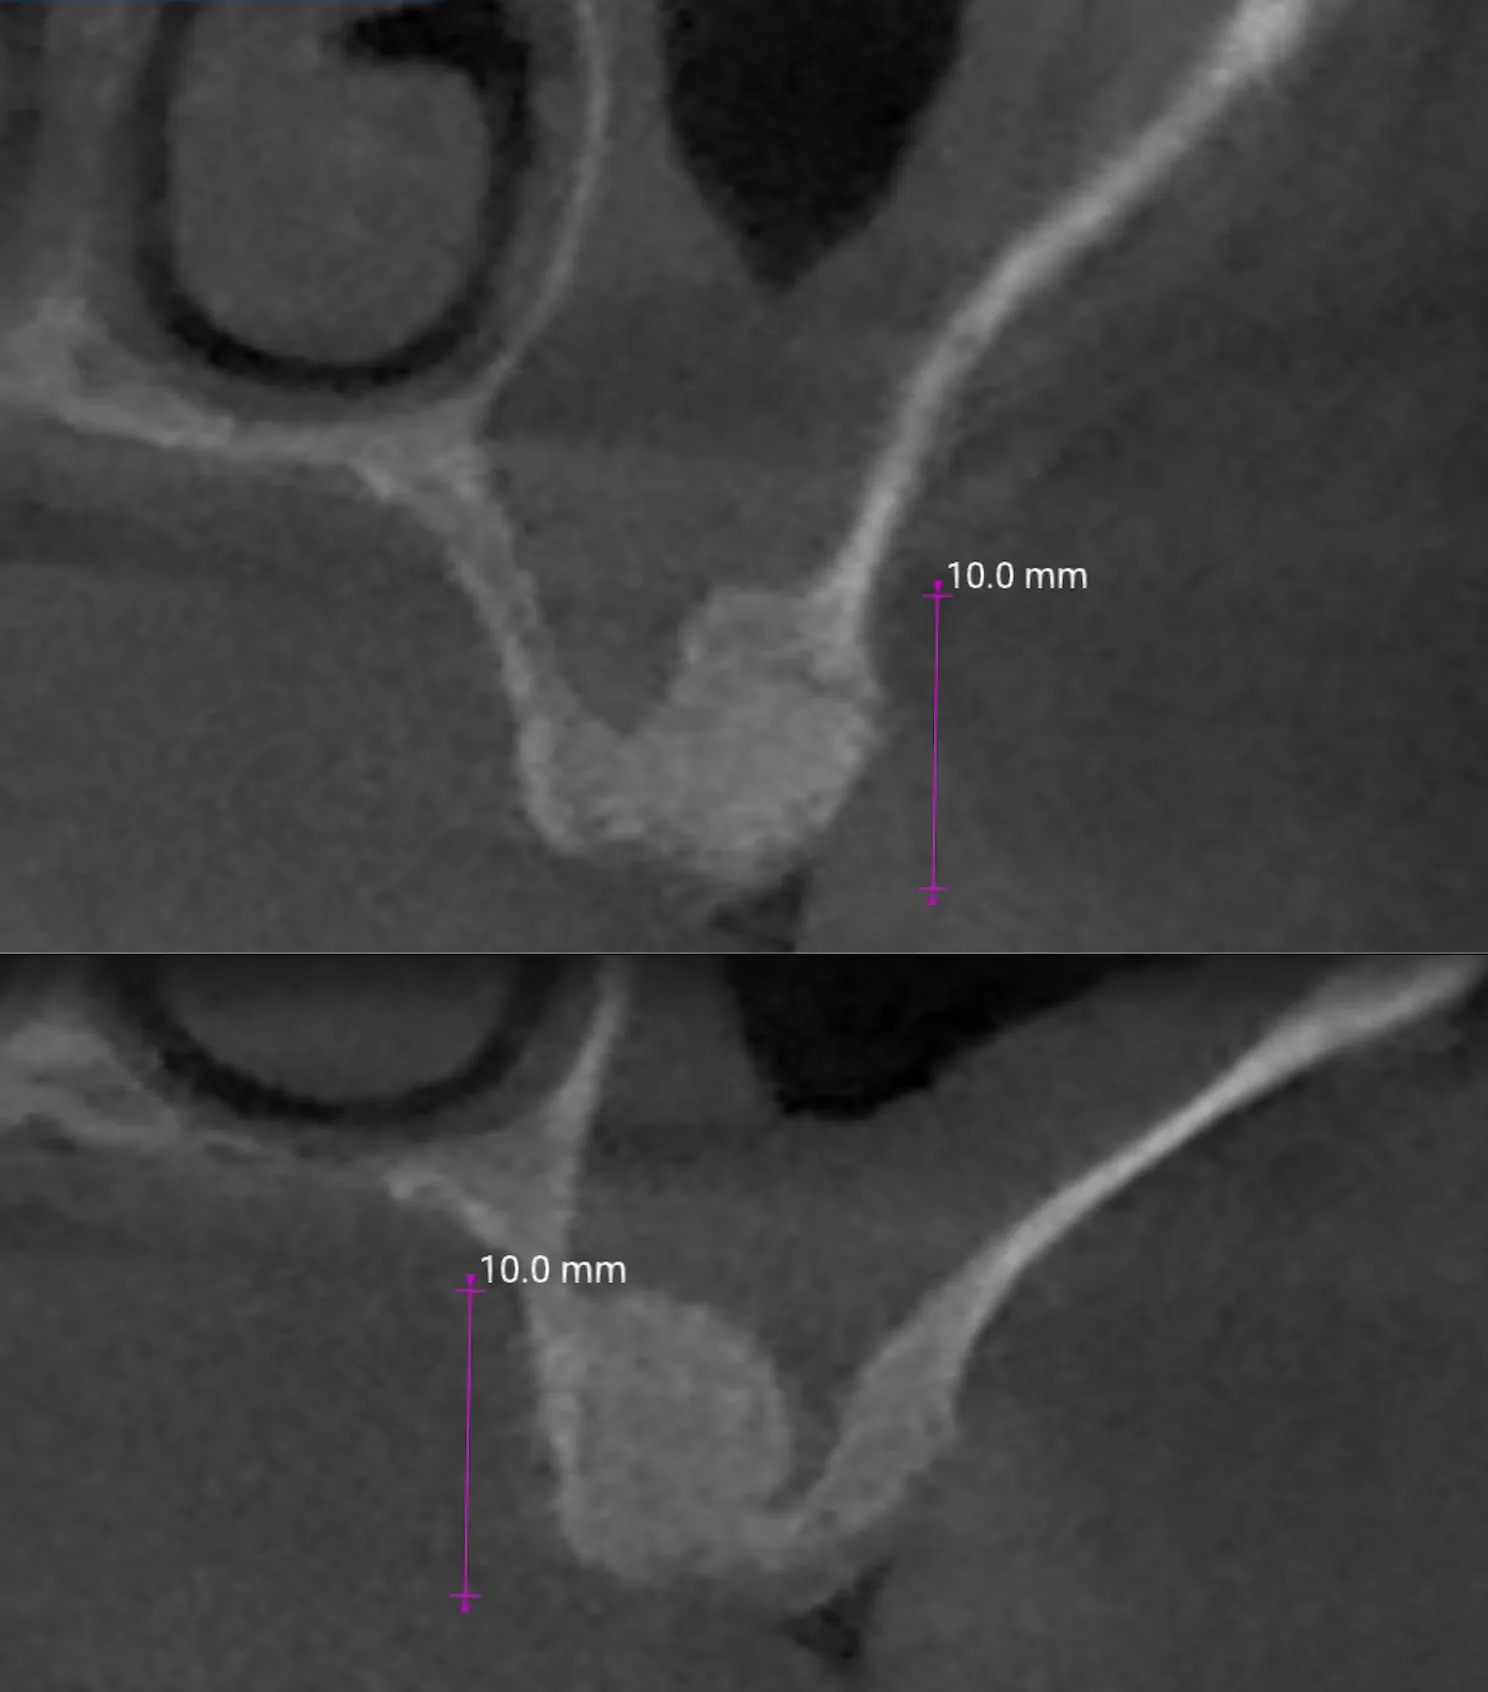

Follow-up CBCT a 2 mesi

Il controllo tomografico a 2 mesi, nell’immagine che segue, ha mostrato:

- Sollevamento del seno con spazio sub-membranoso occupato da graft/osso neoformato in corrispondenza degli alveoli radicolari

- Riempimento degli alveoli stessi con integrazione del particolato

- Assenza di segni di comunicazione oro-antrale

Si apprezza una progressiva integrazione con l’osso nativo circostante.

Dipende dalla conformazione anatomica e dall’altezza residua di partenza. Nel caso presentato, il follow-up CBCT a 2 mesi mostra un rialzo di circa 10 mm. La letteratura riporta risultati predicibili anche in creste con altezza residua inferiore a 5 mm, con tassi di sopravvivenza implantare del 95,81% a 5 anni (Del Fabbro et al., 2012).